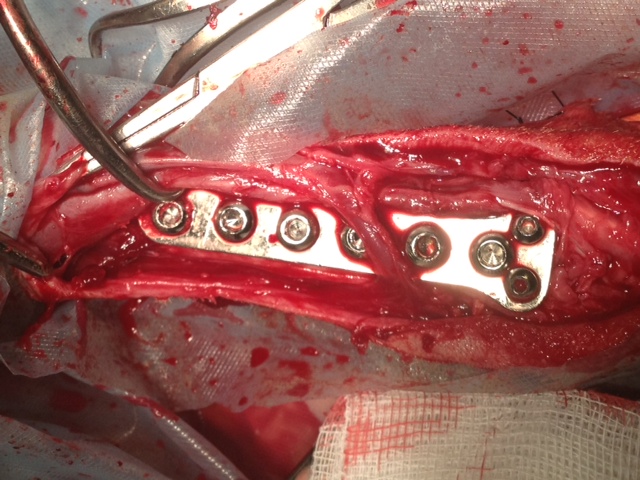

Felipas erste Operation

06Heute hatte Felipa ihren ersten OP-Termin.

Wir waren alle sehr aufgeregt. Und selbst der erfahrene Arzt meinte, es sei eine ungewöhnliche Aktion, denn normalerweise weist nur ein Pfötchen so starke Anomalien auf. Er hatte es noch nicht, dass beide operiert werden müssen.

Felipa war relativ unbeeindruckt von der ganzen Geschichte und tanzte schon kurz nach dem Eingriff wieder auf dem Tisch herum.

In sechs Wochen erfolgt dann die zweite OP.